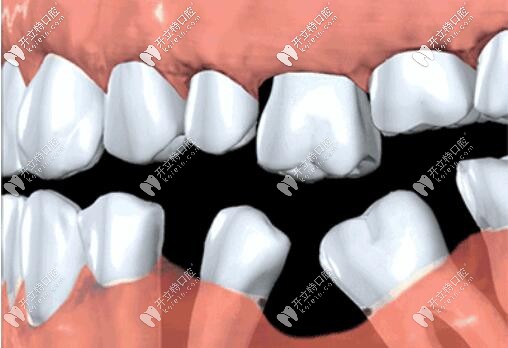

很多人覺(jué)得缺一兩顆牙沒(méi)事,殊不知,長(zhǎng)期咬合不平衡,導(dǎo)致缺牙部位鄰牙傾倒,對(duì)頜牙伸長(zhǎng),整口牙不整齊,都會(huì)影響口腔健康牙齒,加快其他牙脫落。

而且牙齒缺失牙槽骨很快萎縮,再想種牙,有可能骨量不夠,需要植骨,增加額外費(fèi)用,所以缺牙一定要及時(shí)鑲牙,不單是為了健康,也為了幫你省錢(qián)。